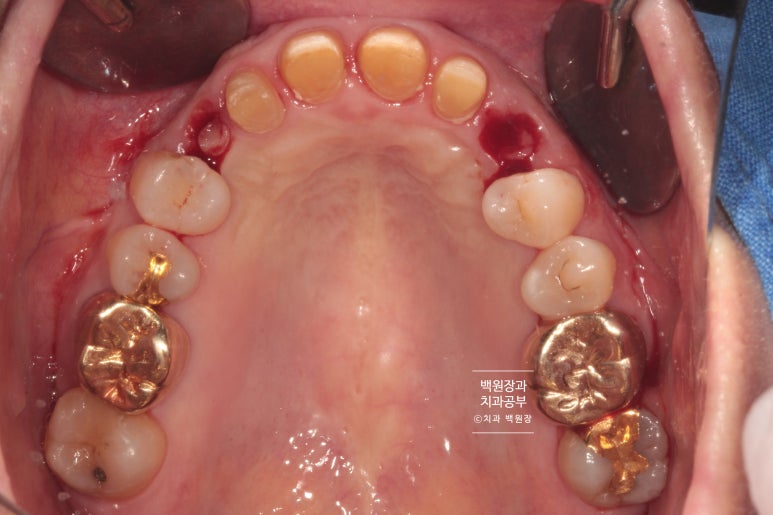

뒤에서 보니 PFM 크라운이었습니다. Porcelain fused metal 이라는 뜻인데요, 메탈 위에 도재를 붙인 형태의 보철물로 옛날에 많이 쓰던 스타일의 보철물이죠.

이렇게 크라운을 여러개 만들 때 가능하면 최대한 낱개로 제작해야합니다. 옛날엔 치과의사의 편의로 붙이는 형태인 splinted crown을 많이 사용했었는데... 치아에도 잇몸에도 아주 안좋은 형태의 보철물이에요!

씹는면에서 바라보았을 때도 자연스러운 모양과 색상을 관찰할 수 있습니다.